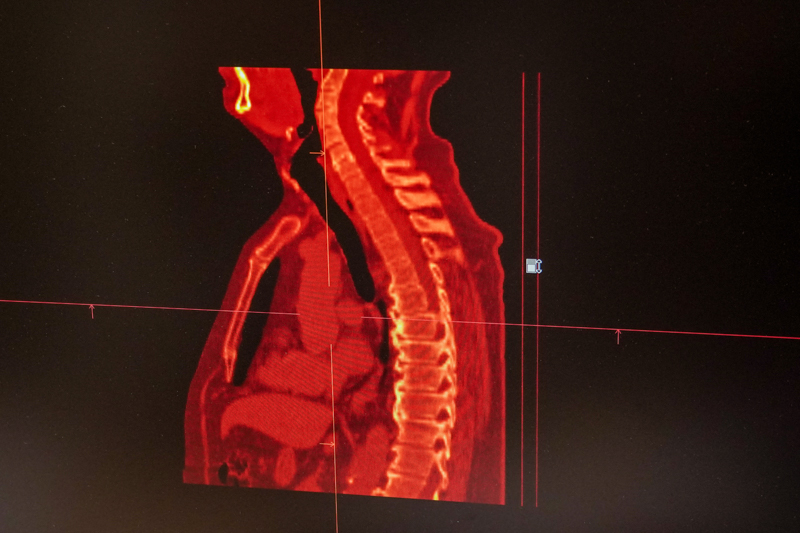

– Вот поступила пациентка, которая находится на динамическом диспансерном наблюдении после операции на щитовидной железе в 1999 году. Благодаря новому методу исследования мы теперь можем на предельно ранних сроках отследить рецидив. Но в данном случае обрадовали человека и самих себя: операция 22 года назад проведена в радикальном объеме, рецидивов не обнаружено. А вот другой свежий случай. Женщина с раком молочной железы пожаловалась лечащему онкологу на боли в пояснице. Тот направил ее в наше отделение. И – видите, вот в этом позвонке засвечен метастаз, – показывает Иван Чикунов изображение, сканированное новым аппаратом.

Очажок высвечен очень маленькой, но яркой точкой. Классическое КТ или МРТ сканирование такое не разглядит. Рентген – тем более.